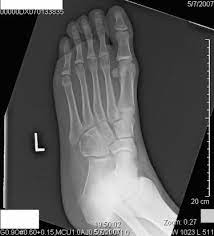

Pain from bone tumors can originate from within the bone. Symptoms of a bone tumor may include: As you learn more about bone cancer, you may become more confident in making treatment decisions. The world health organization has identified 82 different benign and malignant foot lesions. Basal cell cancers may appear as pearly white bumps or patches that may ooze or crust and look like an open sore. Although rare, bone tumors can occur in the foot and ankle. Occasionally a mass or swelling in the area. Grade 1 (g1) means the cancer looks much like normal bone tissue. Sometimes, people with bone sarcoma do not have any of these changes. Each of these types of cancer has their own set of symptoms and treatment, but the main symptom in all of these is a swelling or ulcer on the foot or toe. Bone cancer can weaken the bone it's in, but most of the time the bones do not fracture (break). A benign bone tumor of the foot will manifest as a lump, with or without pain, whereas bone cancer is most often accompanied by pain at the location of the tumor. Whether primary or metastatic, cancer in the bones may present with symptoms such as increasing pain, swelling and/or a more sudden intense pain from a pathologic fracture —a fracture that occurs in a bone that has been weakened by the presence of tumor.

Lumps, swellings, fractures, joint tenderness and pain are some common symptoms of bone cancer in ankle and foot. Squamous cell carcinoma is the most common form of cancer on the skin of the feet. Early on, the pain may only occur at night, or when you are active. When a bone tumor grows, it presses on healthy bone tissue and can destroy it, which causes the following symptoms: The bone may look ragged, or it may appear to have a hole in it.

Primary bone cancer is rare, making up around 0.2 percent of all cancers, according to the american society of clinical oncology. Aside from looking like a changing mole, a melanoma on the foot can appear as a: Osteosarcoma, the most common bone cancer, usually happens to people ages 10 to 30 and most often starts in the arms, legs, or pelvis. Keep friends and family close. Grade 3 (g3) means the cancer looks very abnormal. Foot melanoma is a type of cancer which affects the skin cells of the feet. Bone cancer is rare, making up less than 1 percent of all cancers. A benign bone tumor of the foot will manifest as a lump, with or without pain, whereas bone cancer is most often accompanied by pain at the location of the tumor. Basal cell cancers may appear as pearly white bumps or patches that may ooze or crust and look like an open sore. They work to destroy the tumor or slow down the growth of cancer cells. Local treatments focus on just the bone or bones where the cancer spread. Bone infection in foot is relatively common, especially in the presence of other infectious processes in the foot. Lumps, swellings, fractures, joint tenderness and pain are some common symptoms of bone cancer in ankle and foot.